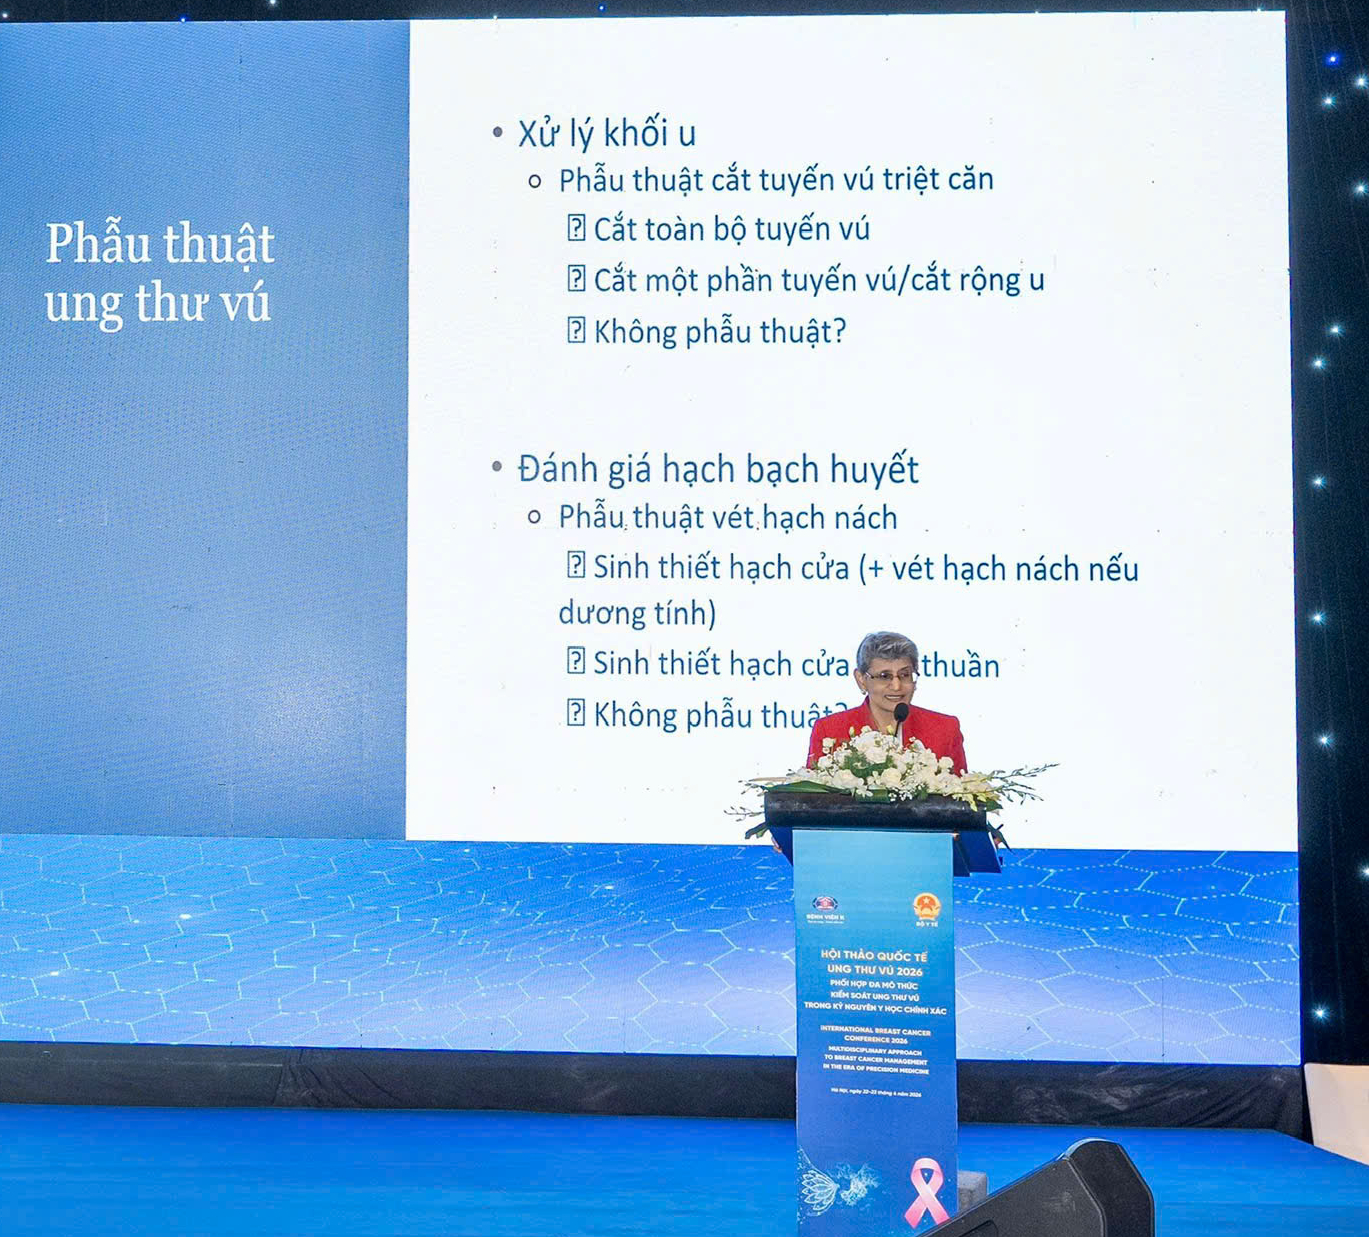

Các chuyên gia quốc tế trao đổi, tham luận tại hội thảo quốc tế về ung thư vú do Bệnh viện K tổ chức.